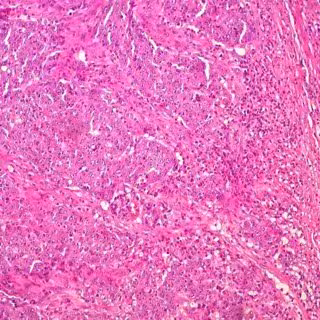

Cáncer de colon - UCM - Archivo